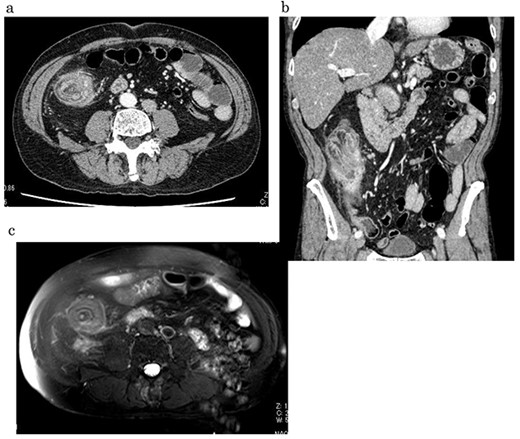

A 59-year-old man was followed up for a year by a dermatologist for psoriasis vulgaris. During this time, he suffered repeated occurrences of cecal diverticulitis diagnosed by contrast-enhanced computed tomography (CT) and was referred to our department for detailed examination and treatment. On examination, he had symptoms associated with subileus such as abdominal distension and pain. Colonoscopy showed a mass with circumferential stenosis in the ascending colon. The surface of the mass showed vascular congestion without malignant findings (Fig. 1a,b). An endoscope could not pass through the stenosis, and enema colonography showed complete stenosis (Fig. 2). Contrast-enhanced CT/magnetic resonance imaging (MRI) revealed a thick wall from the ileocecal region to the ascending colon, which was accompanied by a ring-shaped, layered appearance of mucosal and muscular layers (Fig. 3a–c).

Contrast-enhanced CT/MRI showed increased wall thickness from the ileocecal region to the ascending colon (a, b), which was accompanied by a ring-shaped and layered appearance of the mucosal and muscular layers (c).

Our patient’s endoscopic macroscopic findings showed vascular distension and redness at the mucosal surface and circular stenosis. CT and MRI images showed ring-shaped and layered mucosal and muscular layers, suggesting a target sign. Because reduction by barium enema examination and endoscopy could not be achieved, we performed intestinal resection of the stenotic site including the diverticulitis via a surgical procedure. During the operation, we were alert to the potential for adhesions between the intestinal walls and surrounding tissues related to the inflammation and abscess of the diverticulitis, which caused reduction through nonsurgical conservative treatment to be difficult. The present patient’s pathophysiology should be kept in mind as one differential diagnosis of intestinal wall thickening in patients with chronic diverticulitis.